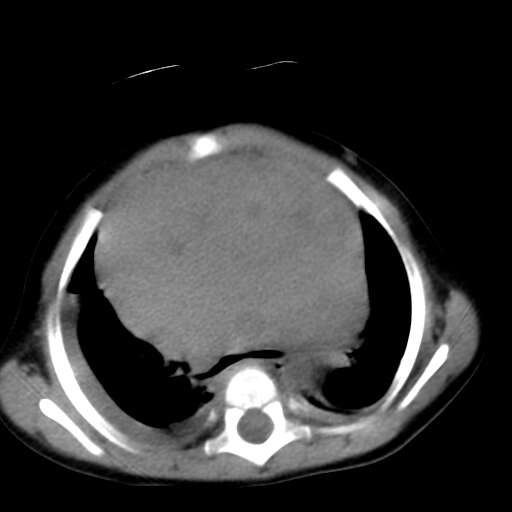

患儿1y,女,因支肺炎经dr检查发现前上纵膈占位而行ct检查,肿块与心血管脂肪间隙模糊消失,可见斑点状钙化,未见脂肪成分,双侧胸水,考虑侵袭性胸腺瘤

1、定位:前上纵隔,血管及头臂干前方,胸腺部位。

2、巨大实性肿块,其内见小片状低密度灶和少许点状钙化。

3、双侧胸腔积液,提示肿瘤恶性可能。

4、双肺下也背侧肺间质水肿改变。